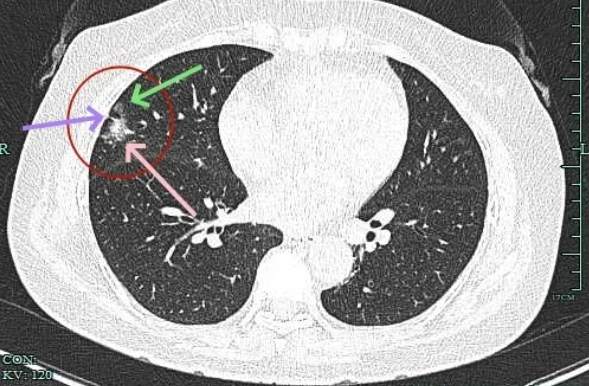

典型毛刺征,磨玻璃部分瘤肺边界清,表面不平,灶内密度不均。

实性成分占比高,表面不平,有细毛刺征,整体感觉有一定收缩力。